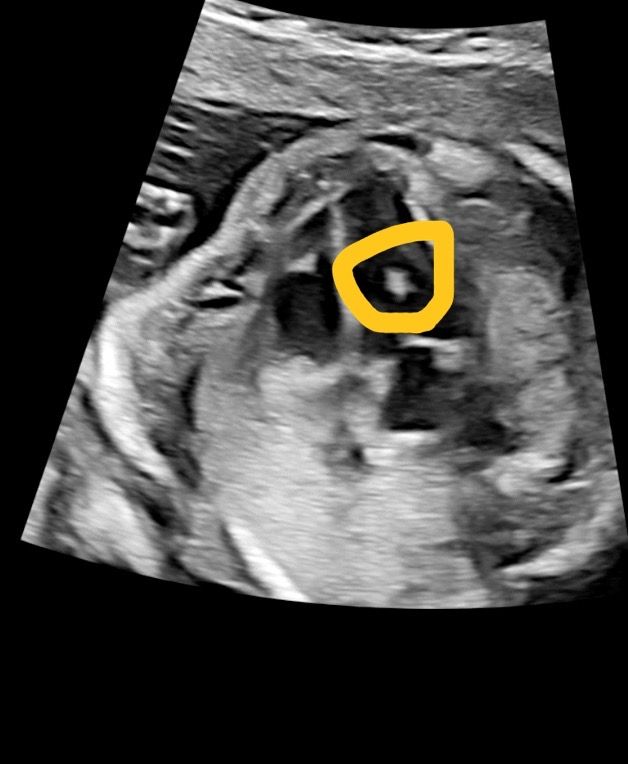

태아 21주 정밀초음파 좌실심 고음영,

좌심실에 고음영이 있는다는데

다운증후군 애들이 많이 가지고 있다는데.. 맞나요?

좌심실 고음영이라는건 도대체 어떤 건가요? ㅠㅠ안좋는건가요? 또 나중에 안없어지나요?구체적으로 말해주세요

다운증후군에서 심장이상이 자주 동반되니 심장초음파가 필요하다는 이야기이며

심장초음파 소견이 비정상이라고해서 다운증후군인 것은 아닙니다.

좌심실에 고음영이 보인다는 소견만으로는 어떤 진단도 내릴 수 없습니다.